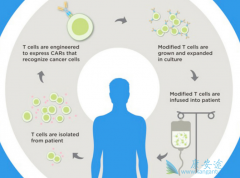

CART疗法 在全球范围内受到包括学者、医生、患者、投资人在内的如此大量的关注和期待,起初是源于一个白血病小女孩Emily和她的神奇抗癌经历。先一起来看看Emily的神奇故事吧! Emily是一位来自美国加州的小女孩,5岁时不幸被诊断为患上了急性淋巴细 ...

CART细胞疗法 在实体瘤中仍需不断探索。CD19 CAR-T细胞是首个获得商业批准的转基因治疗。遗传工程化T细胞作为癌症精准治疗,其中最重要的科学挑战是CAR-T细胞如何治疗实体瘤,目前最突出的例子就是颅内使用IL13RαCAR T细胞治疗多发脑恶性胶质瘤,使肿 ...

2012年,6岁的急性淋巴细胞白血病小女孩Emily在无药可医的情况下,尝试了Carl June实验室的研究性 CART细胞治疗 ,奇迹至此发生,治疗后她一直健康的生存至今。CD19 CART细胞治疗自此以百米速度进入公众视野和临床实践。其中CAR,即嵌合抗原受体,是该治 ...